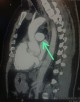

: aorta ascendente

: estomago

: aorta descendente